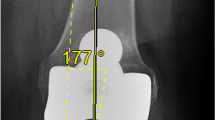

The image delivered by fluoroscope (Fig. 3) was analysed by the surgeon in two steps. First, the surgeon observed the centring of the rod into the circle found on the aiming plate. A well-centred position for the rod on the horizontal diagonal of the circle indicates that the radiographic image was taken on a perpendicular direction upon the aiming plate and subsequently in the same perpendicular plane with the two condylar holes. If the rod was not observed at the centre of the circle, the C-arm was repositioned by circulating personnel and a new image was taken. Second, the surgeon analysed the fluoroscopic image for the position of the rod in reference to H. Any possible transverse distance between the rod and H was evaluated, and its magnitude was measured through the marker points found on the aiming plate. Normally, the distance between the two points corresponds to an angle of 2° when the receiver part of the C-arm is close to the aiming plate. When the deviation angle was >0.5° on the fluoroscopic image, the surgeon adjusted manually the bone resection using either a rasp or a 2° surface cut guide.

The mean postoperative HKA angle was 180° (range, 176–185°; SD, 2°) in group F and 179.9° (range, 175–186°; SD, 3°) in group C. The SD in group F was statistically significantly lower (p = 0.025, Levene’s test). The number of outliers >3° outside of the HKA range was 4 (7.7 %) in group F and 10 (19.2 %) in group C (p = 0.15, Fisher exact test). The frontal femoral component alignment was 90° ± 2° in group F and 90° ± 3° in group C (p = nonsignificant (n.s.)). The number of outliers >3° varus or valgus in the frontal component alignment was 5 (9.6 %) in group F and 10 (19.2 %) in group C (p = n.s.). The frontal tibial component alignment was 90° ± 3° in group F and 89° ± 3° in group C (p = n.s.). The number of outliers >3° varus or valgus deviation in the frontal tibial alignment was 6 (11.5 %) in group F and 11 (21.1 %) in group C (p = n.s.). The posterior inclination of the cemented tibia base plate component was 3° ± 3° in group F and 4° ± 3° in group F. In total, 29 of 52 knees in the fluoroscopic group had surgical adjustments of the femoral surface (range 1° to 2°), and 14 of 52 knees had adjustments of tibia alignment (range 1° to 2°). The fluoroscopic time varied from 2 to 6 s and DAP from 3 to 27 u Gy/cm2.